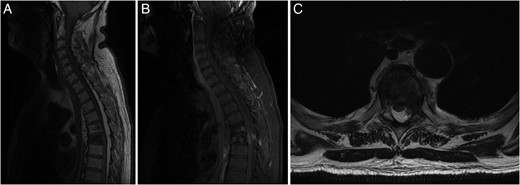

Investigation for his recent ataxia and sensory changes included CT of his thoracic spine (Fig. 1B) and whole spine magnetic resonance imaging (MRI) scan (Fig. 2), which demonstrated marrow infiltrative disease involving the T6 and T5 vertebra, corresponding to the findings seen on previous imaging. The appearance of the T6 fracture compared with CT imaging from 6 months previously had remained largely unchanged. However, there was a significant paravertebral (especially left epidural) disease at T6, likely related to an underlying infiltrative lesion resulting in compression of the thecal sac without spinal cord oedema (Fig. 2). Interestingly, superimposed dorsal epidural lipomatosis was also seen extending along the cervicothoracic spinal canal, from C7 to T10, most severe at the T5 and T6 levels, further contributing to canal stenosis and likely causing the patient's symptoms.

(A) Sagittal T1-weighted MRI showing the T5 and T6 vertebral compression fractures with extensive hyperintense SEL from C7 to T10. (B) Sagittal FAT SAT T1-weighted MRI following gadolinium contrast showing contrast enhancing paravertebral disease mainly at T6 level, with enhancing epidural disease with further canal stenosis from epidural lipomatosis. (C) Axial T2-weighted MRI displaying through T6 level showing compression and right lateral displacement of the thecal sac and spinal cord.